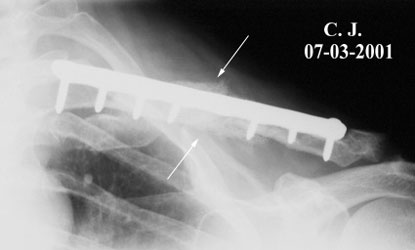

Image n° 3:

the fracture is healed

(03 - 07 - 2001)